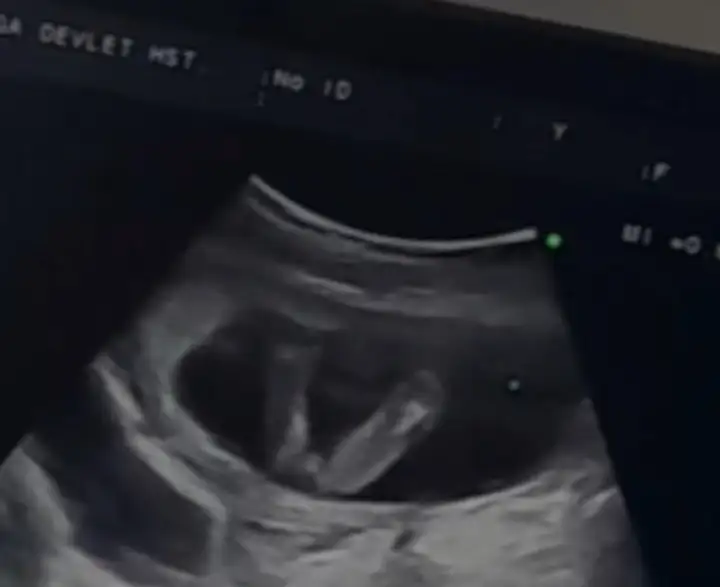

İlerleyen zamanlarda daha da iyi olursunuz inşallah. Bizim bacak arası bir öyle bir böyle emin değiliz bu yüzden . Bakın tekrar atayım. Bacak arasındaki kordon mudur artık ayrıntılıda çıkacakAmin canım benim, evet benimki büyük olasılıkla kız doktor bacak arası çıkıntı göremiyorum dedi

Arkadaşlar kimse mi yorum yapmadıKızlarr merhaba 14+6 da randevum vardı bacak arası burayı gösterdi bana doktorumneye benziyor sence dedi bende erkek sanırım dedim kendimi tutamadım ağlayınca belki iri dudaklıdır belki değişir sonra diye teselli etti doktor beni sağlığıyla gelsin önceliğimiz bu ama bu haftalarda erkek bebişlerin pipisi kocaman oluyor benim bebeğim pipisi mi küçük yoksa dudakları mı büyük

Çok sağolun amin. Evet sizin bebeğinizdeki çıkıntı benimkisine göre daha fazla. Erkek olma olasılığı da var. O nedenle biraz daha beklemek en iyisi. Dediğiniz gibi bazen kordon yanıltabiliyor.İlerleyen zamanlarda daha da iyi olursunuz inşallah. Bizim bacak arası bir öyle bir böyle emin değiliz bu yüzden . Bakın tekrar atayım. Bacak arasındaki kordon mudur artık ayrıntılıda çıkacak

sizinki çok belirgin erkek gibi. kordon bazen yanıltabiliyor ama sizin her açıdan çıkıklık var bana erkek gibi geldi :) kız mı istiyordunuz?Arkadaşlar kimse mi yorum yapmadı

Kız istiyordum birazda edindim rüyalardan falan ikinci foto bir başka bebeğin o bariz belli pipisi olduğu ama benim ki minicik duruyor şaştım kaldım artıksizinki çok belirgin erkek gibi. kordon bazen yanıltabiliyor ama sizin her açıdan çıkıklık var bana erkek gibi geldi :) kız mı istiyordunuz?